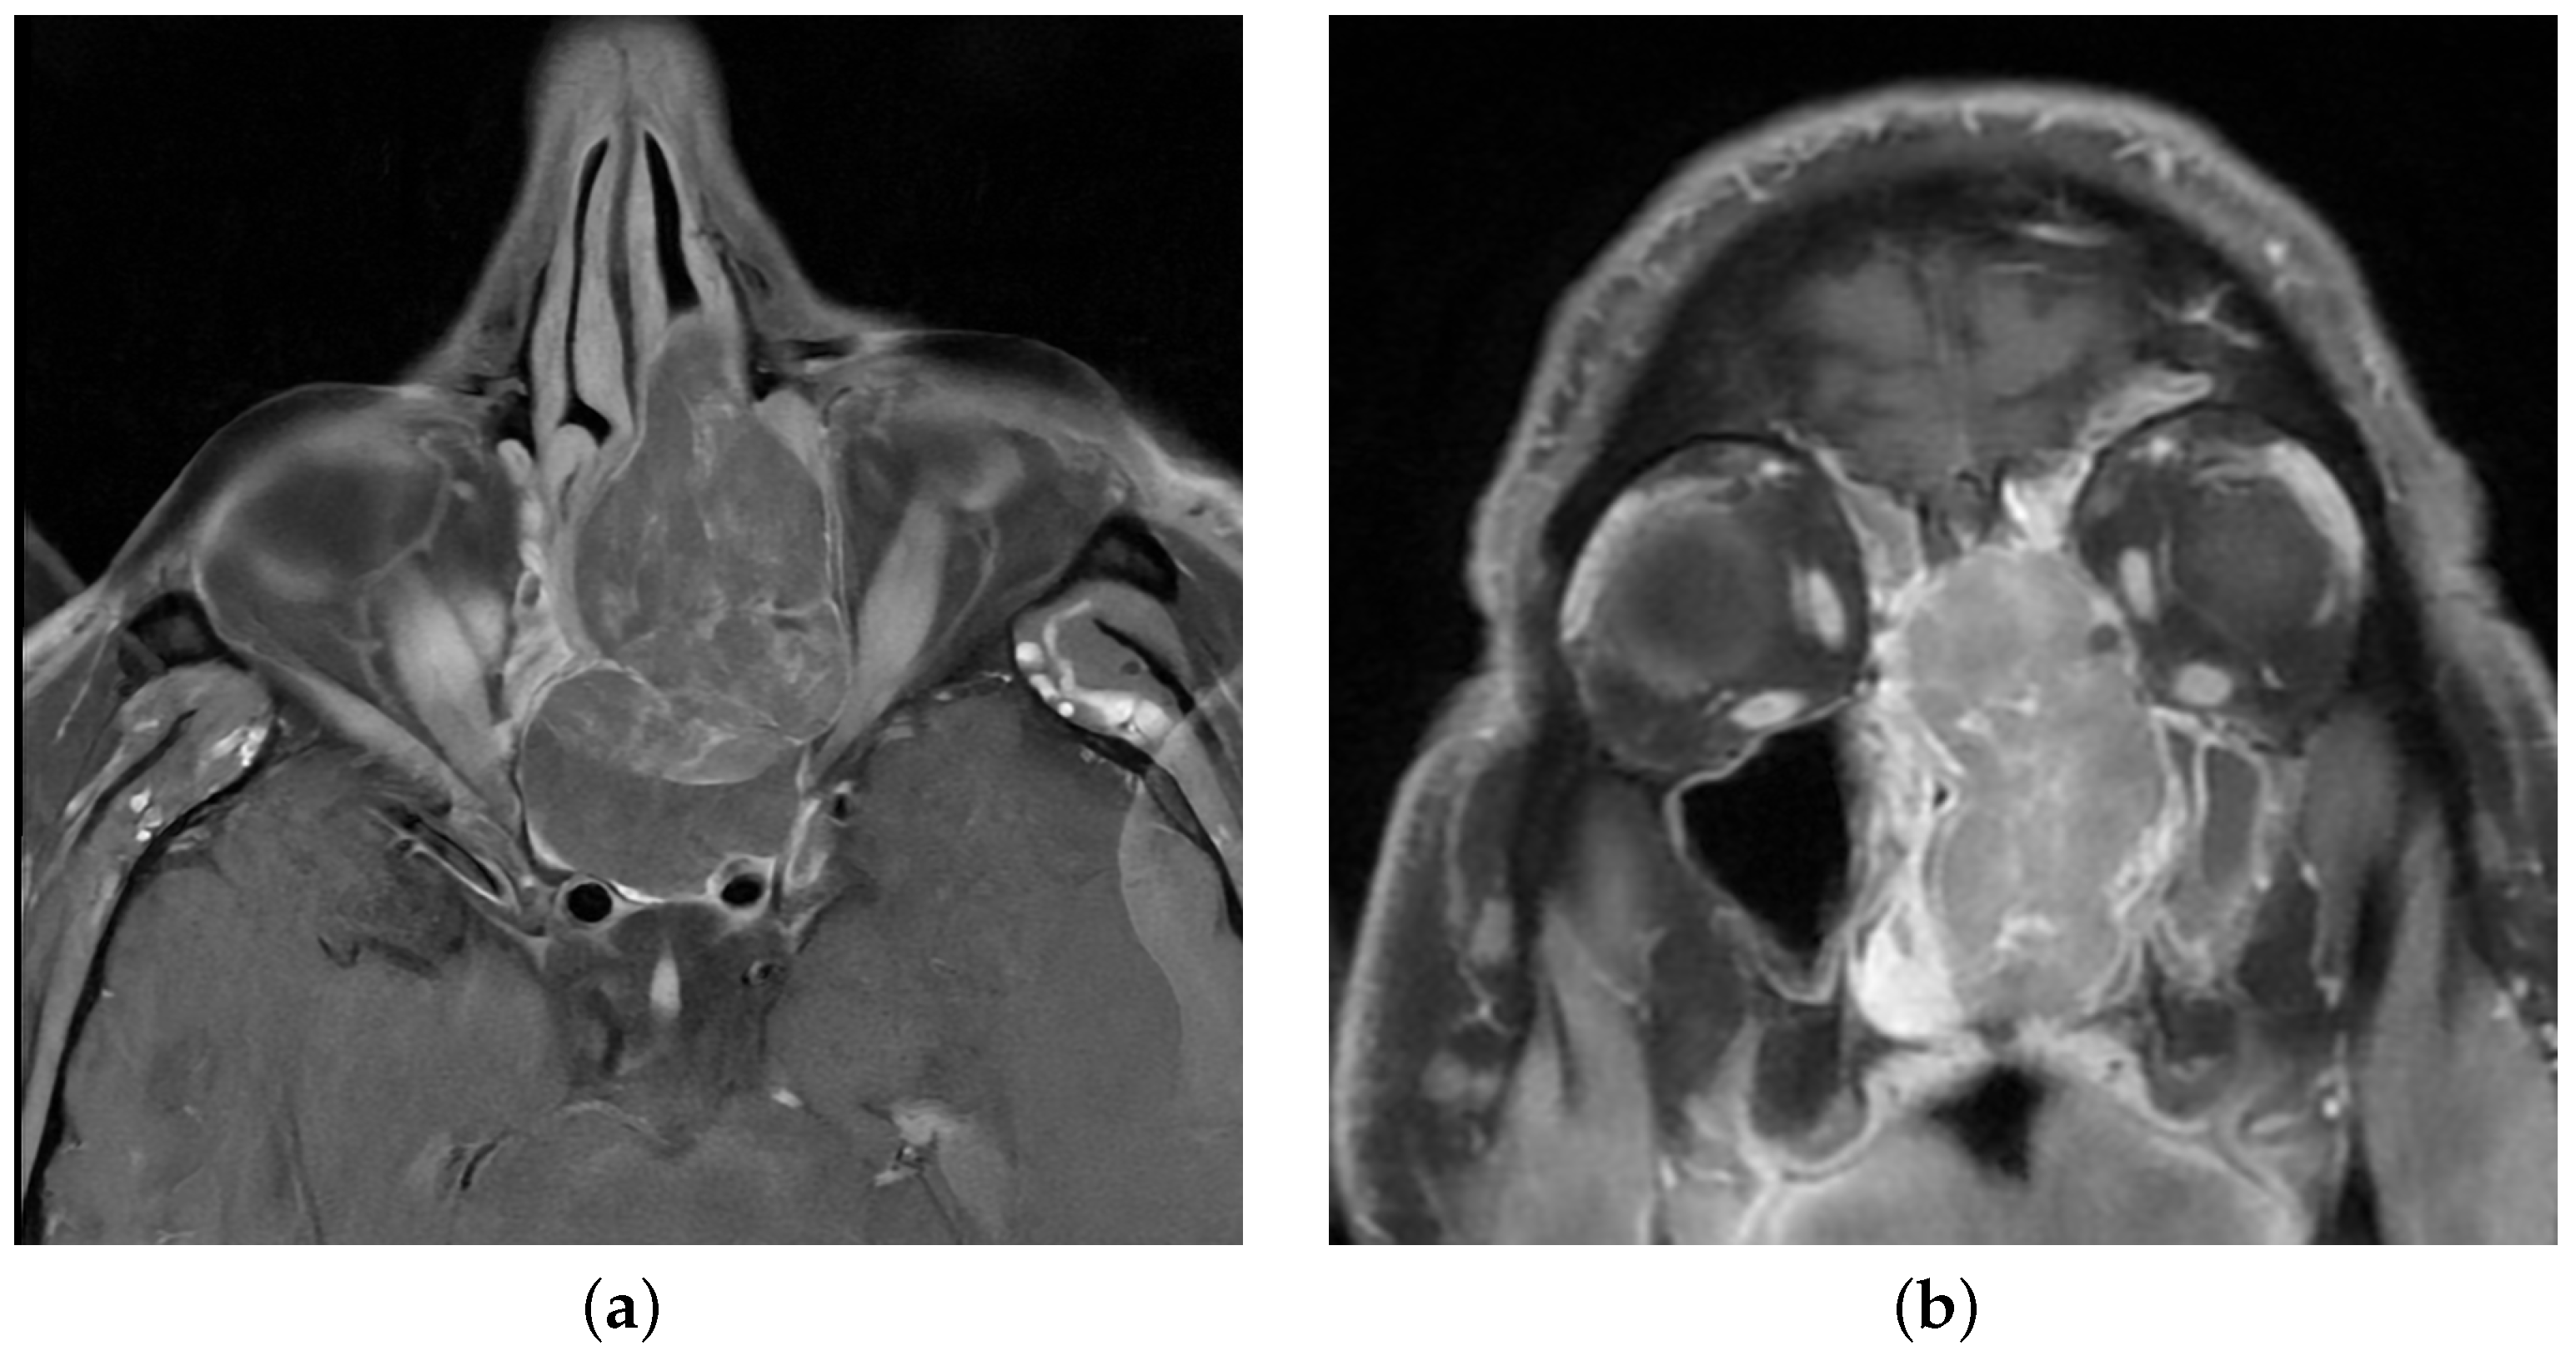

| MRI | Magnetic resonance imaging |